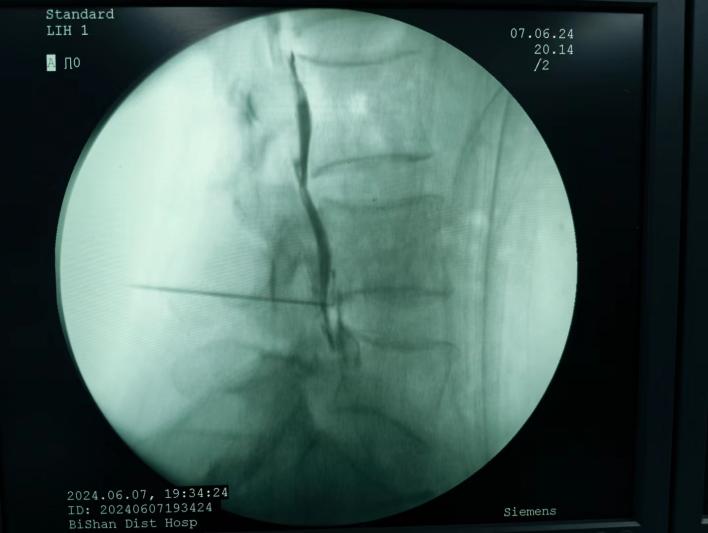

椎間盤射頻消融術、膠原酶椎間盤化學消融術